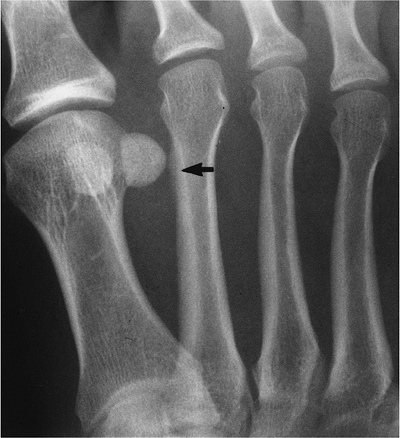

Fractures of the fifth metatarsal base are common in children and adults.

Fractures are categorized as proximal or distal.

Proximal fractures are divided into three zones (Fig. 6-34).

Zone 1, avulsion fractures; Zone 2, Jone’s fractures caused by forefoot

adduction; Zone 3, typically athletic stress fractures. -

Distal fractures (Dancer’s fracture) are usually the result of a direct blow.

-

Treatment of fractures in Zone 1 and distal fractures is conservative. Fractures in Zones 2 and 3 may require internal fixation.

FIGURE 6-34 Oblique radiograph demonstrating the three zones of the proximal fifth metatarsal. There is an ununited Jone’s fracture (arrow) in Zone 2.